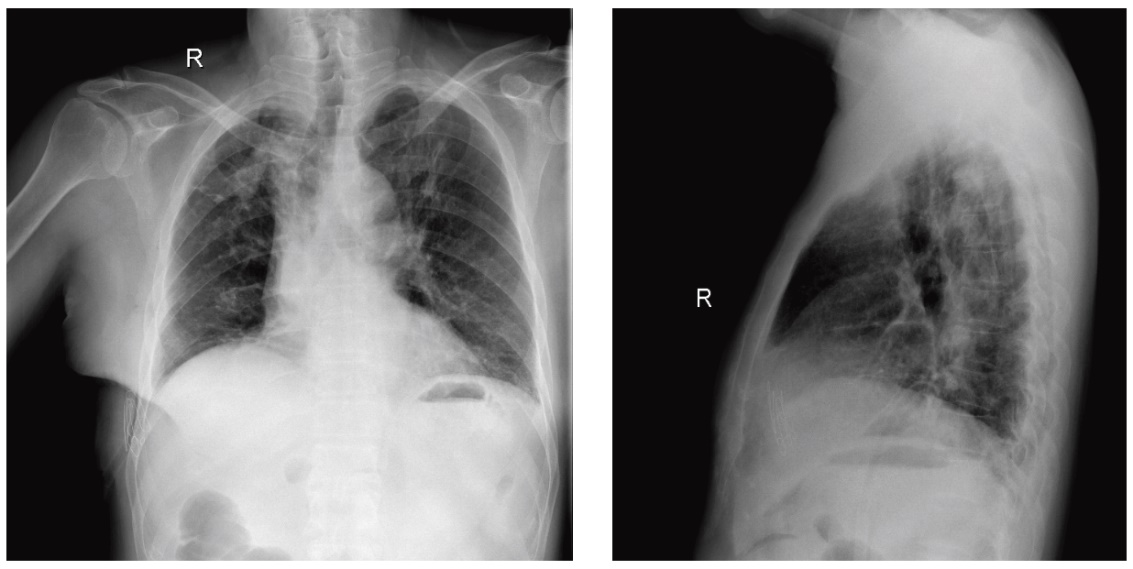

患者术后胸部X线